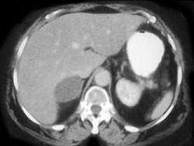

问题 女,45岁,满月脸、向心性肥胖2年余,实验室检查:血、尿皮质醇增高,请结合CT图像,作出诊断()

选项 A.左肾上腺腺瘤 B.左肾上腺腺癌 C.左肾上腺转移瘤 D.左肾上腺嗜铬细胞瘤 E.左肾上腺增生

答案 A